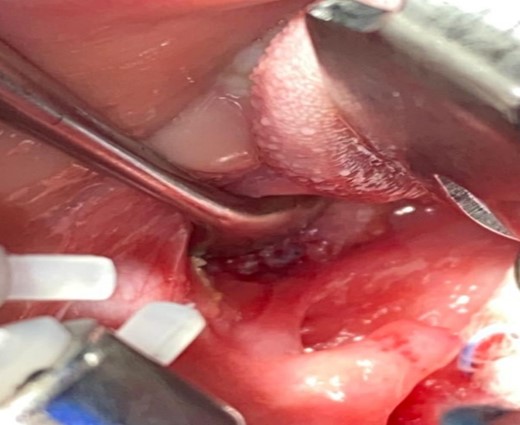

After draping and sterilisation, the small left-sided neck punctum was identified, probing of the fistula tract by a lacrimal probe was done, followed by the insertion of an arterial catheter inside the fistula tract (Fig. 6). The amount of methylene blue added was 0.01 ml per 2 ml of fibrin glue, and a total of 4 ml of this mixture was injected. This mixture allows the glue to be dyed adequately and does not inhibit its solidification. The arterial catheter was totally inserted, about 7 cm in length, and injection of methylene blue with fibrin glue was performed using an arterial catheter inside the tract. An elliptical incision was made around the fistula opening, followed by dissection of the tract. The tract was obvious, firm and colored with methylene blue. The tract was easily dissected without the need to remove extra tissues around it. Another superior incision, a step ladder incision, was made as the tract was long. The tract followed to its entry into the tonsillar fossa, which was ligated. The internal carotid artery, internal jugular vein, hypoglossal nerve and glossopharyngeal nerve were all identified and preserved. Bilateral tonsillectomy was performed, and the tract was visualised within the left tonsil (Figs 1–4). The left tract at the tonsillar bed after the tonsillectomy was ligated and cauterised. Then bilateral auricular sinus excision is done. The patient was then seen after 3 months of surgery and was doing well.

The left tonsill after removal and tract opening seen clearly on its surface.